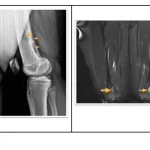

その最中, 単顆型人工膝関節置換の手術中の後輩医師から連絡が入りました.

「手術中に大伏在静脈をを損傷したあと, 結紮して止血したが, その後に急に腫れてきた」

とのこと.

急遽ヘルプで手術室へ.

手洗いを済ませ, 縫合されていた創部を開けて内部を確認しました.

血管損傷部位は適切に処置されており, 活動性出血もなし.

問題ないと判断し, 手術室を後にしました.